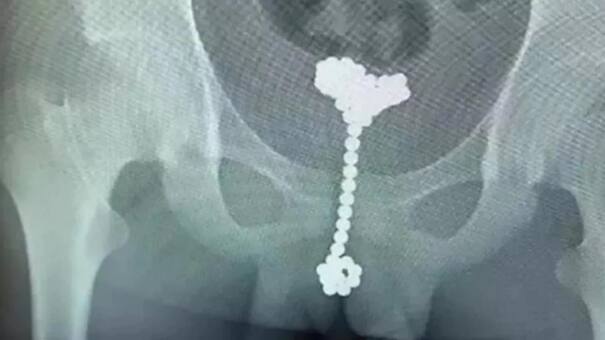

Se encontró con manchas en su cuerpo y fuertes dolores en sus piernas. Ante la situación, decidió concurrir a un hospital y lo más llamativo fue lo que le dijeron los médicos: le comunicaron que un parásito había entrado por su miembro y le estaba dejando los huevos (crías) dentro de su cuerpo... pero que ya estaba fuera de peligro.

¿Cómo mejoró? Recibió antibióticos por parte de los especialistas del centro médico y al no tener resultados le hicieron nuevos estudios y le diagnosticaron que padecía esquistosomiasis, una infección causada por un gusano parásito que se encuentra en las aguas dulces en regiones tropicales. Fue entonces cuando atacaron al parásito con un medicamento que mató la infección. Por el suceso, quedó muy débil y le dijeron que había un 30 por ciento de posibilidades de que se recupere por completo dentro de 10 años.